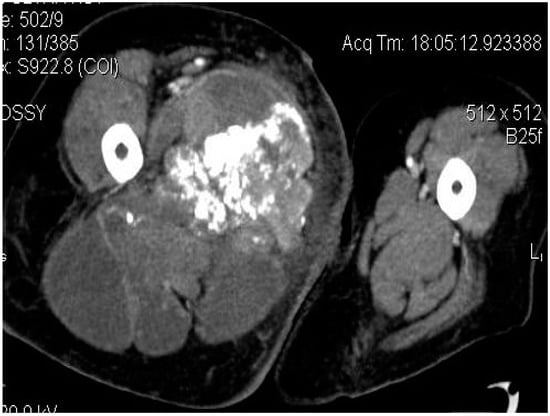

2.2. Imaging Examinations